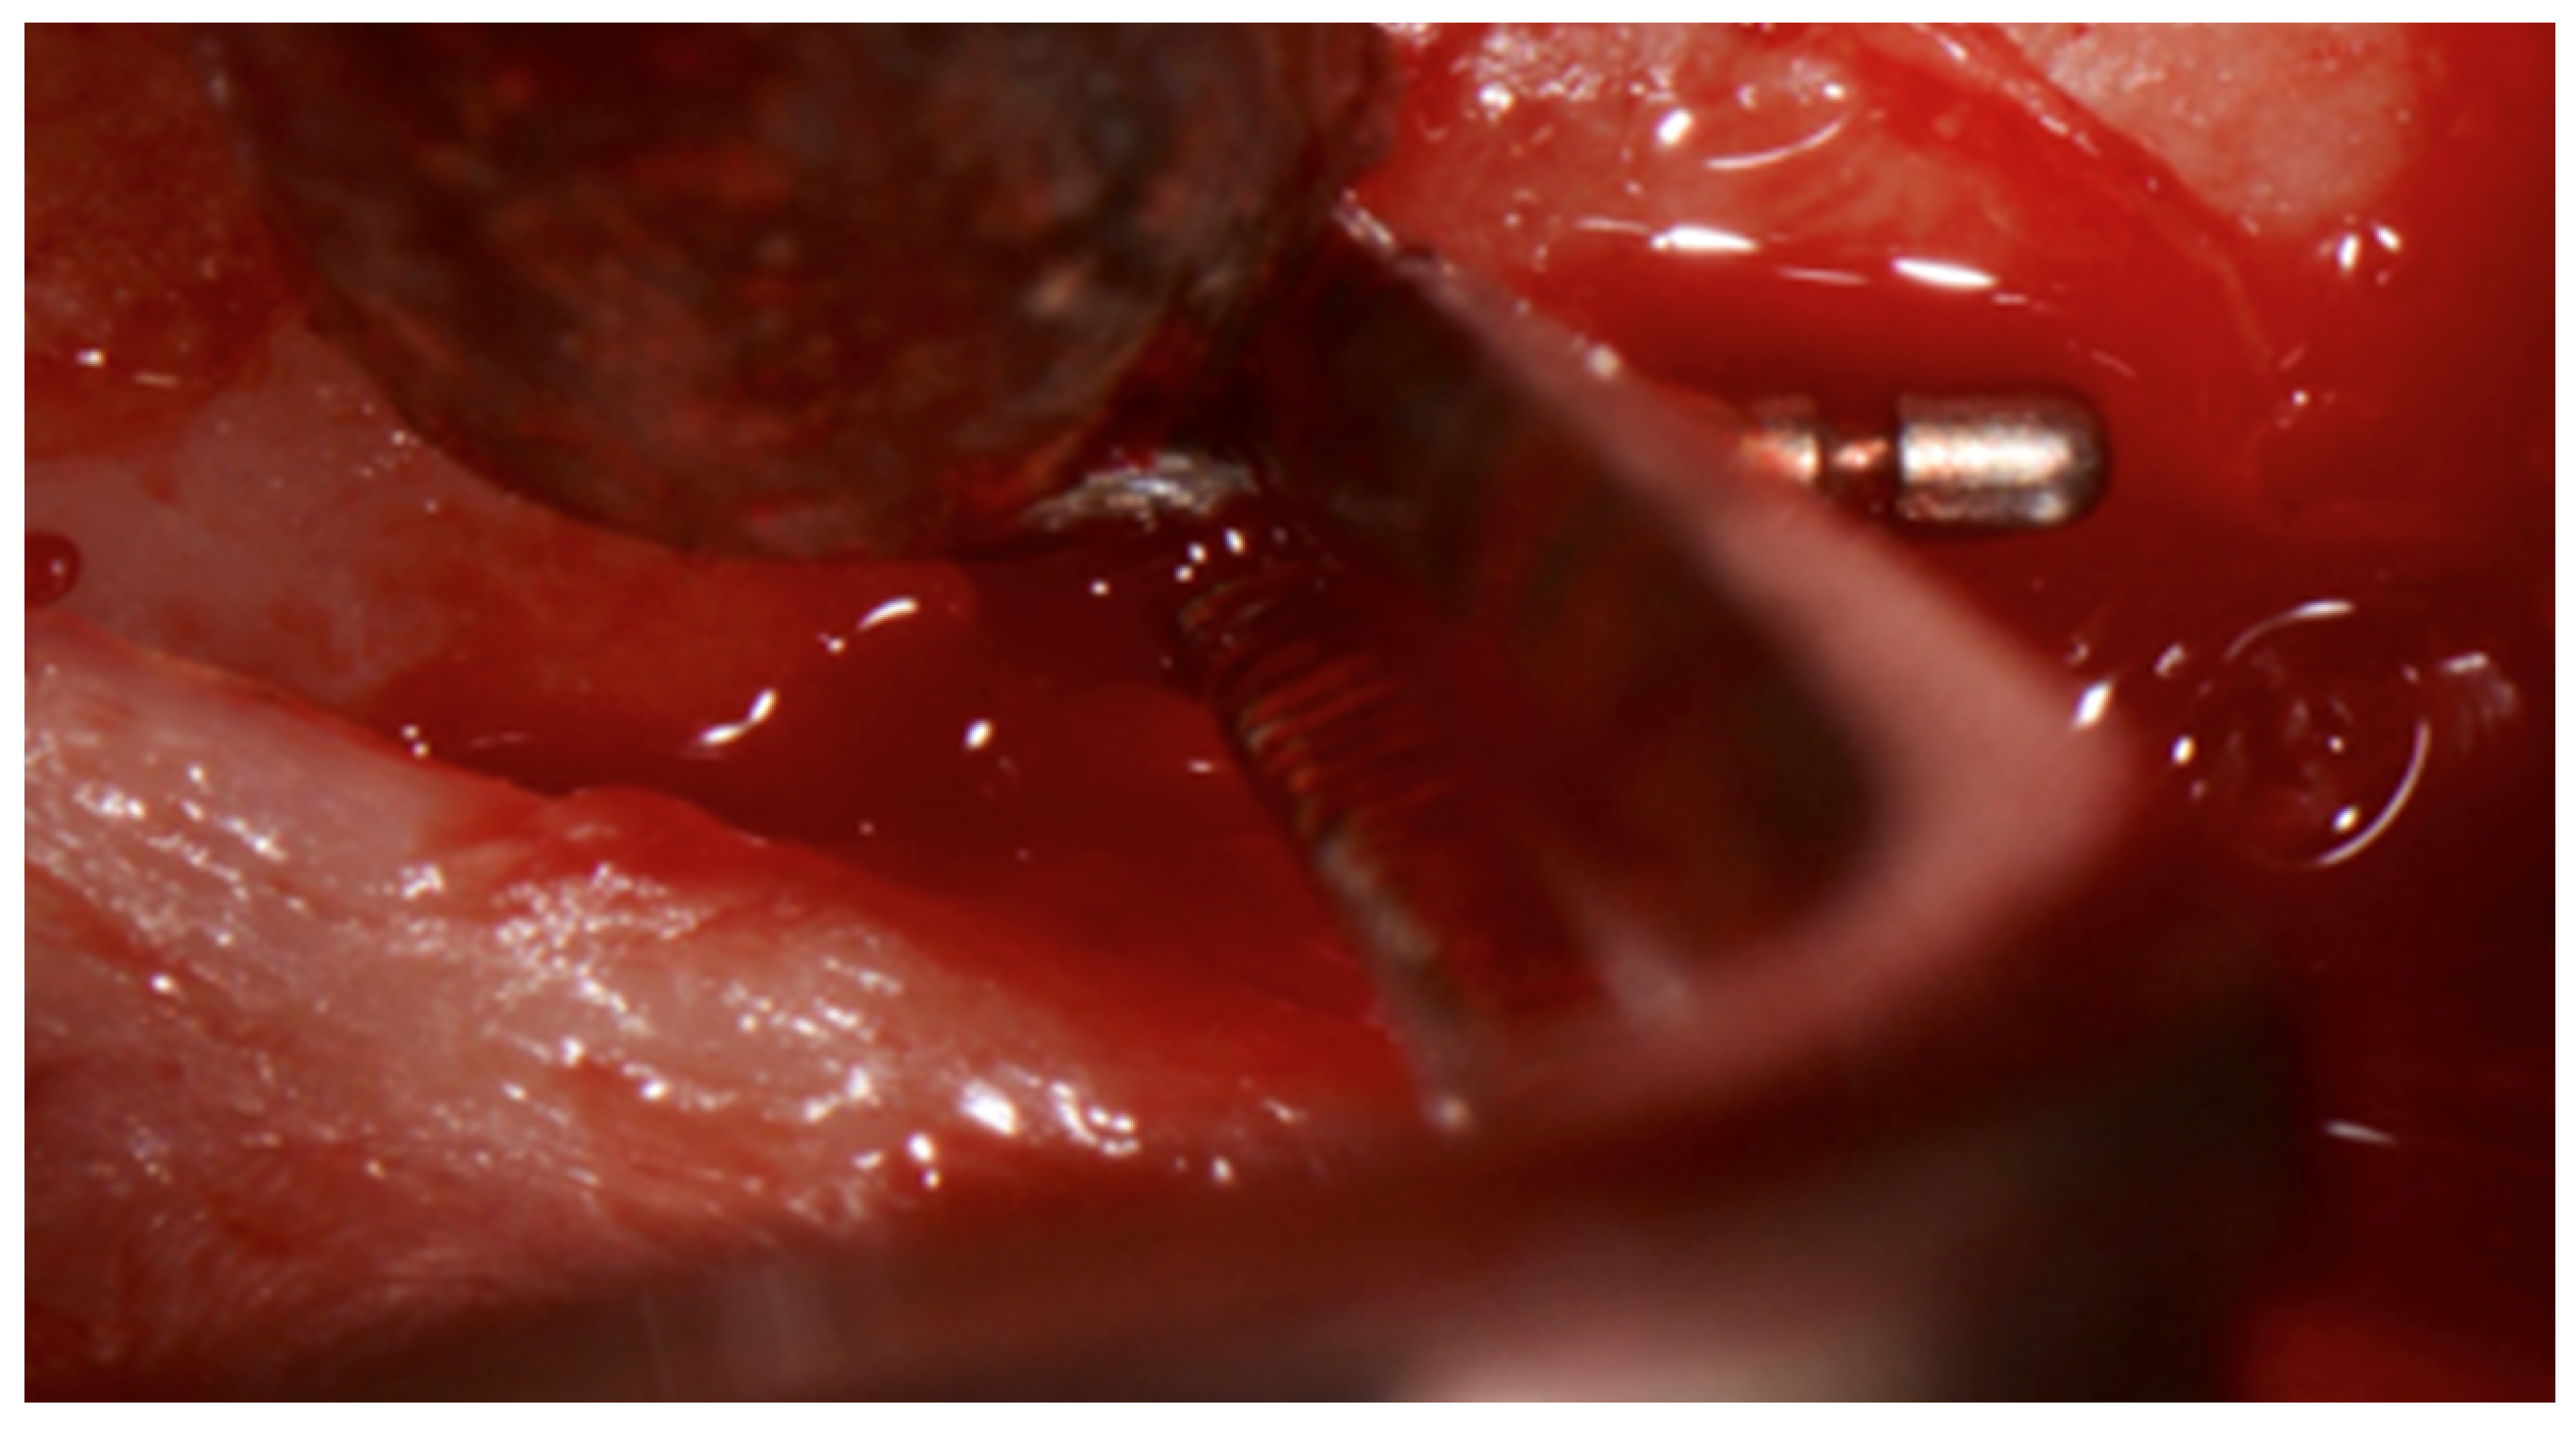

4. Therapy

In December 2019, region 45 was operated and the fractured instrument tip removed (Figure 5 and Figure 6).

Figure 5.

In situ image showing the removal of the broken periodontal probe tip from buccal, which was removed with pliers after careful luxation.